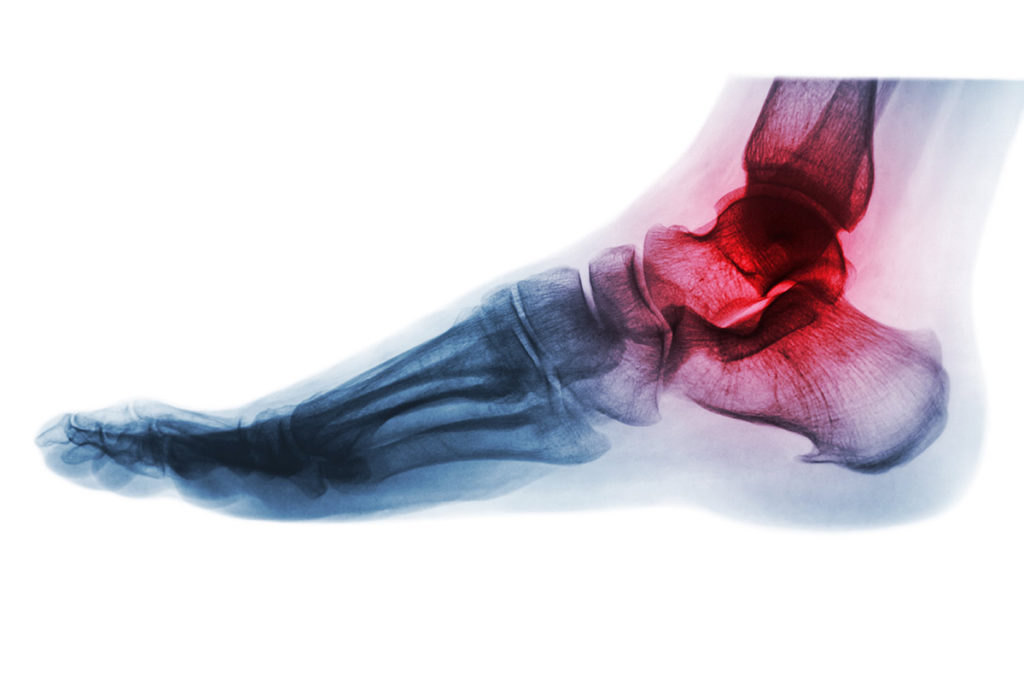

La artritis y la artrosis son dos enfermedades que afectan a las articulaciones,, pero no hay que confundirlas, ya que ambas son muy diferentes entre sí. En el caso de la artritis nos encontramos ante una inflamación de las articulaciones mientras que en el caso de la artrosis estamos ante una patología de origen “mecánico”.

La artritis causa dolor incluso en estado de reposo e independientemente de la disminución de la actividad. Ello se debe a que se trata de una inflamación de las articulaciones y, como tal, produce dolor aun estando en reposo. La artritis es una enfermedad de origen inflamatorio, afecta a la membrana sinovial y, en determinados casos, puede ser extremadamente dolorosa

Por su parte, la artrosis es una enfermedad de origen “mecánico” ya que el dolor se produce en el momento en que las articulaciones entran en movimiento. El origen de la artrosis se debe a una alteración del cartílago que se desgasta de forma gradual hasta que desaparece, dejando los huesos en contacto entre sí y sin la protección de la amortiguación que proporciona el cartílago. Se trata, por tanto, de una degeneración de las articulaciones, en la que no hay ningún tipo de inflamación de origen interno, por lo que la persona que la sufre no corre el riesgo de que la patología se extienda o afecte a otros órganos. En el caso de la artrosis el dolor aparece solo cuando las articulaciones están en movimiento. Suele afectar especialmente a las manos y la columna vertebral.

- Principales diferencias entre artritis y artrosis en cuanto a los síntomas. En el caso de la artritis se pueden manifestar diversos síntomas: dolor, enrojecimiento de la zona afectada, hinchazón (edema), calor, rigidez y, en ocasiones, deterioro del estado general, con fiebre y astenia. Por el contrario los síntomas de la artrosis son dolor, rigidez y deformidad ósea.